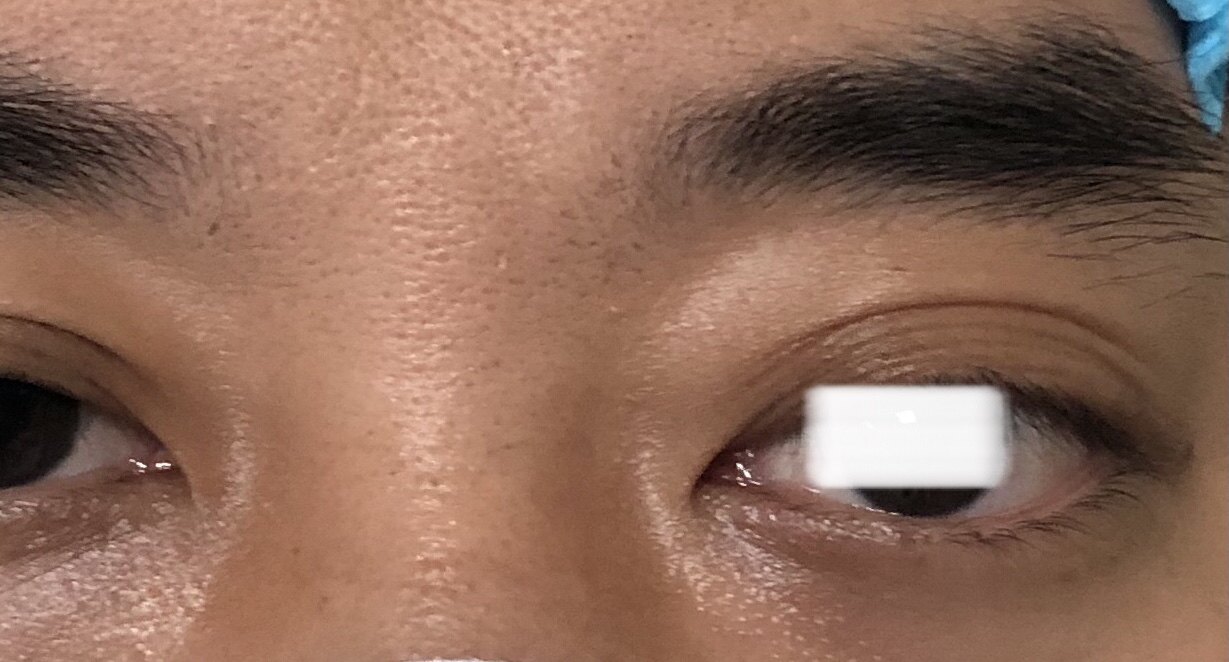

患者年轻男性,因为拍片偶尔发现肿物就诊。

仔细观察有轻度下垂和眼球突出